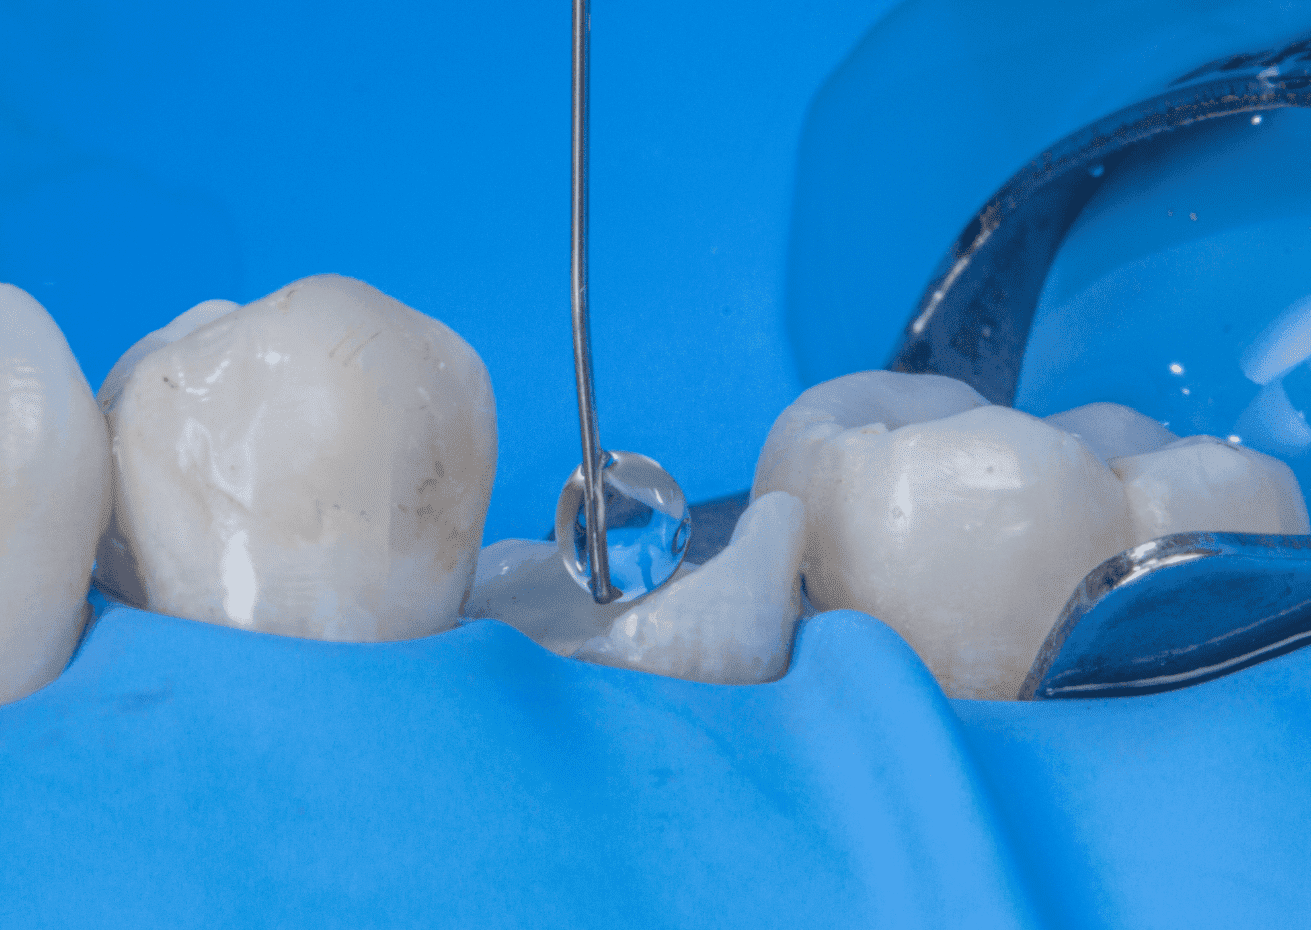

No planejamento reabilitador, foi reabilitado com dois pinos Whitepost SYSTEM cimentados com a combinação de sistema adesivo Ambar Universal APS e cimento resinoso dual Allcem CORE, que também foi utilizado para construção do núcleo de preenchimento.

A restauração final foi realizada utilizando scanner digital e coroa em resina vitrocerâmica BRAVA Block usinada em CAD-CAM, também foi cimentada com cimento resinoso dual Allcem CORE.